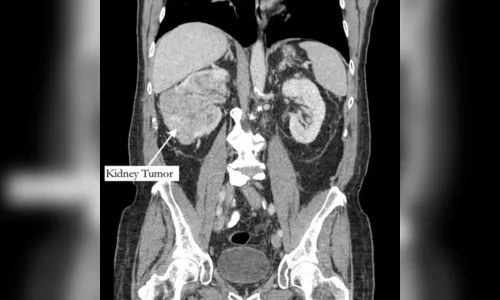

De acordo com as informações do jornal "New York Post", o aposentado sempre achou que sua dor era por conta de uma fratura, mas, no fim, soube que se tratava de um tumor no rim e de um trombo tumoral, um tumor que se estende até um vaso sanguíneo.

O exame, encaminhado a um urologista, identificou ainda um trombo (coágulo no sangue) que cresceu através da veia renal e preenchia a veia cava, que drena sangue para o coração, e tinha 99% das artérias da coronária bloqueadas, além do fígado quase entrando em falência.

Segundo o diretor de urologia do Hospital Phelps, no estado de Nova York, Michael Grosso, o bloqueio de veias por conta do tumor e do trombo era o que explicava a dor no pé do aposentado, já que os sintomas de câncer no fígado costumam surgir já em uma fase avançada do tumor.

O paciente passou então por uma cirurgia de urgência para remover o tumor. Após 12 horas de uma cirurgia complexa e casada entre médicos de diferentes especialidades, o tumor e o trombo foram retirados e uma ponte de safena foi realizada.